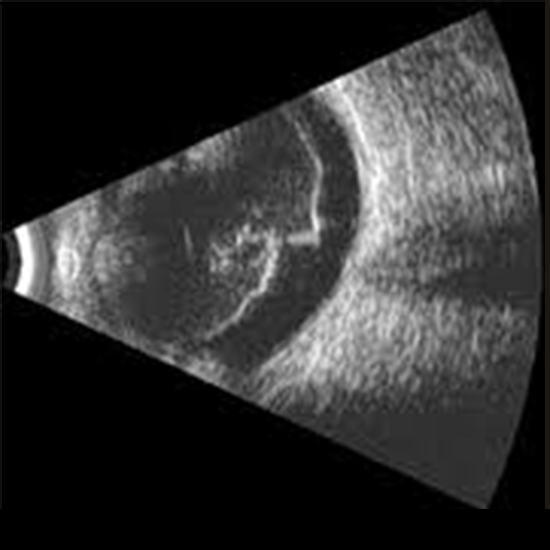

B-scan ultrasonography, or B-scan, is a diagnostic technique used in optometry and ophthalmology to generate a cross-sectional, two-dimensional image of the eye and orbit.

Ultrasound utilises sound waves with a high frequency that go through the eye. Reflections (echoes) of the sound waves create an image of the eye's structure.

A "B scan ultrasonography" test assesses the eye's backside. This test is commonly performed before cataract surgery. A severe cataract restricts the retina's view. In that case, your doctor is unaware of your retinal health. Here, ultrasound aids. We learn if the retina is in position or if something is seriously wrong with it.